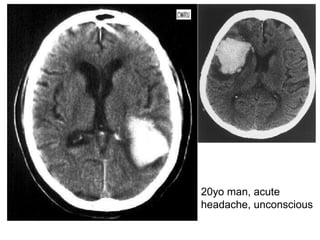

20yo man, acute headache, unconscious

CT brain- hemorrhage Name this Ix? CT scan of brain Describe? Hyperdense (recent hemorrhage, calcified lesion, contrast enhancement) Mass effect: displace compress lat ventricles Midline shift Ventricular dilatation (CSF obs/atrophy of brain tissue) Widened cortical sulci (brain atrophy) Cerebral edema?? Dx? Cerebral hemorrhage  Common causes? Hypertension (Charcot-Bouchard aneurysm) Aneurysm AVM Other Ix? CT/MRI brain angiography Hypodense (black): Neoplasm/infarction Edema (surrounding) Cerebral hemorrhage: usually in the region of the internal capsule by the rupture of the lenticulostriate artery

20yo man, acuteheadache, unconscious

CT brain- hemorrhageName this Ix? CT scan of brain Describe? Hyperdense (recent hemorrhage, calcified lesion, contrast enhancement) Mass effect: displace compress lat ventricles Midline shift Ventricular dilatation (CSF obs/atrophy of brain tissue) Widened cortical sulci (brain atrophy) Cerebral edema?? Dx? Cerebral hemorrhage Common causes? Hypertension (Charcot-Bouchard aneurysm) Aneurysm AVM Other Ix? CT/MRI brain angiography Hypodense (black): Neoplasm/infarction Edema (surrounding) Cerebral hemorrhage: usually in the region of the internal capsule by the rupture of the lenticulostriate artery